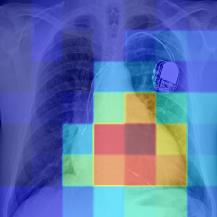

Thoracic disease detection from chest radiographs using deep learning methods has been an active area of research in the last decade. Most previous methods attempt to focus on the diseased organs of the image by identifying spatial regions responsible for significant contributions to the model's prediction. In contrast, expert radiologists first locate the prominent anatomical structures before determining if those regions are anomalous. Therefore, integrating anatomical knowledge within deep learning models could bring substantial improvement in automatic disease classification. This work proposes an anatomy-aware attention-based architecture named Anatomy X-Net, that prioritizes the spatial features guided by the pre-identified anatomy regions. We leverage a semi-supervised learning method using the JSRT dataset containing organ-level annotation to obtain the anatomical segmentation masks (for lungs and heart) for the NIH and CheXpert datasets. The proposed Anatomy X-Net uses the pre-trained DenseNet-121 as the backbone network with two corresponding structured modules, the Anatomy Aware Attention (AAA) and Probabilistic Weighted Average Pooling (PWAP), in a cohesive framework for anatomical attention learning. Our proposed method sets new state-of-the-art performance on the official NIH test set with an AUC score of 0.8439, proving the efficacy of utilizing the anatomy segmentation knowledge to improve the thoracic disease classification. Furthermore, the Anatomy X-Net yields an averaged AUC of 0.9020 on the Stanford CheXpert dataset, improving on existing methods that demonstrate the generalizability of the proposed framework.